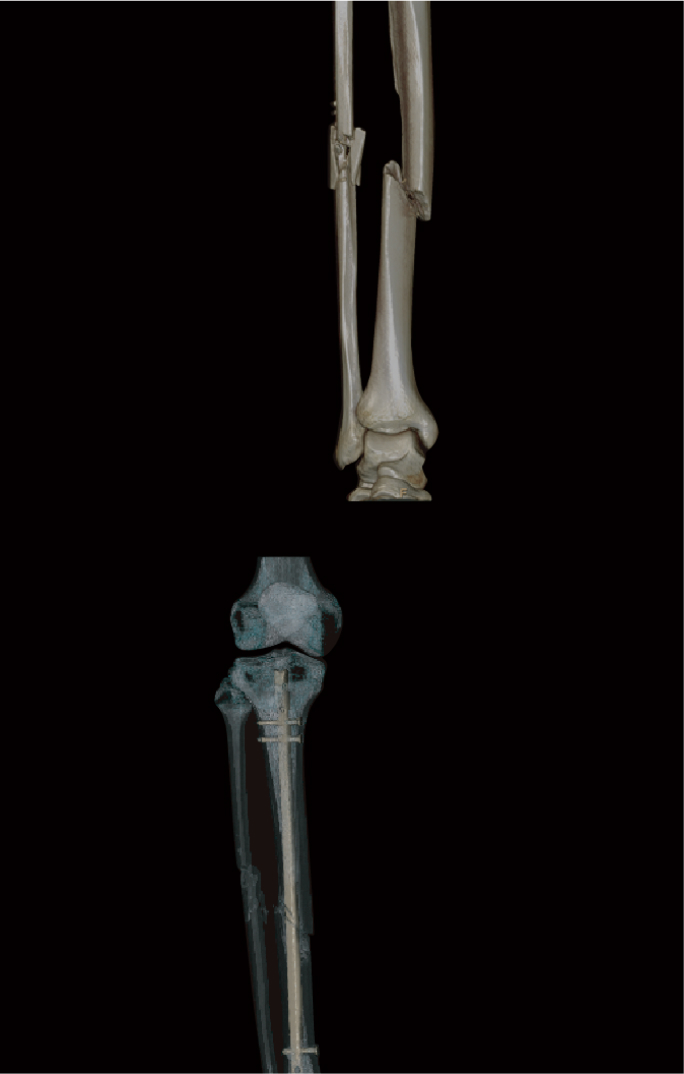

정확한 3D CT 기반 진단 및 수술 Planning을 시작합니다.

정확한 골절의 위치, 각도, 회전 방향까지 분석해 수술계획을 수립하고,

• 02. 최신형 3d 기반 골절 진단 및 수술 planning

• 06. 불유합 없이 튼튼한 고정 3D 맞춤 Planning